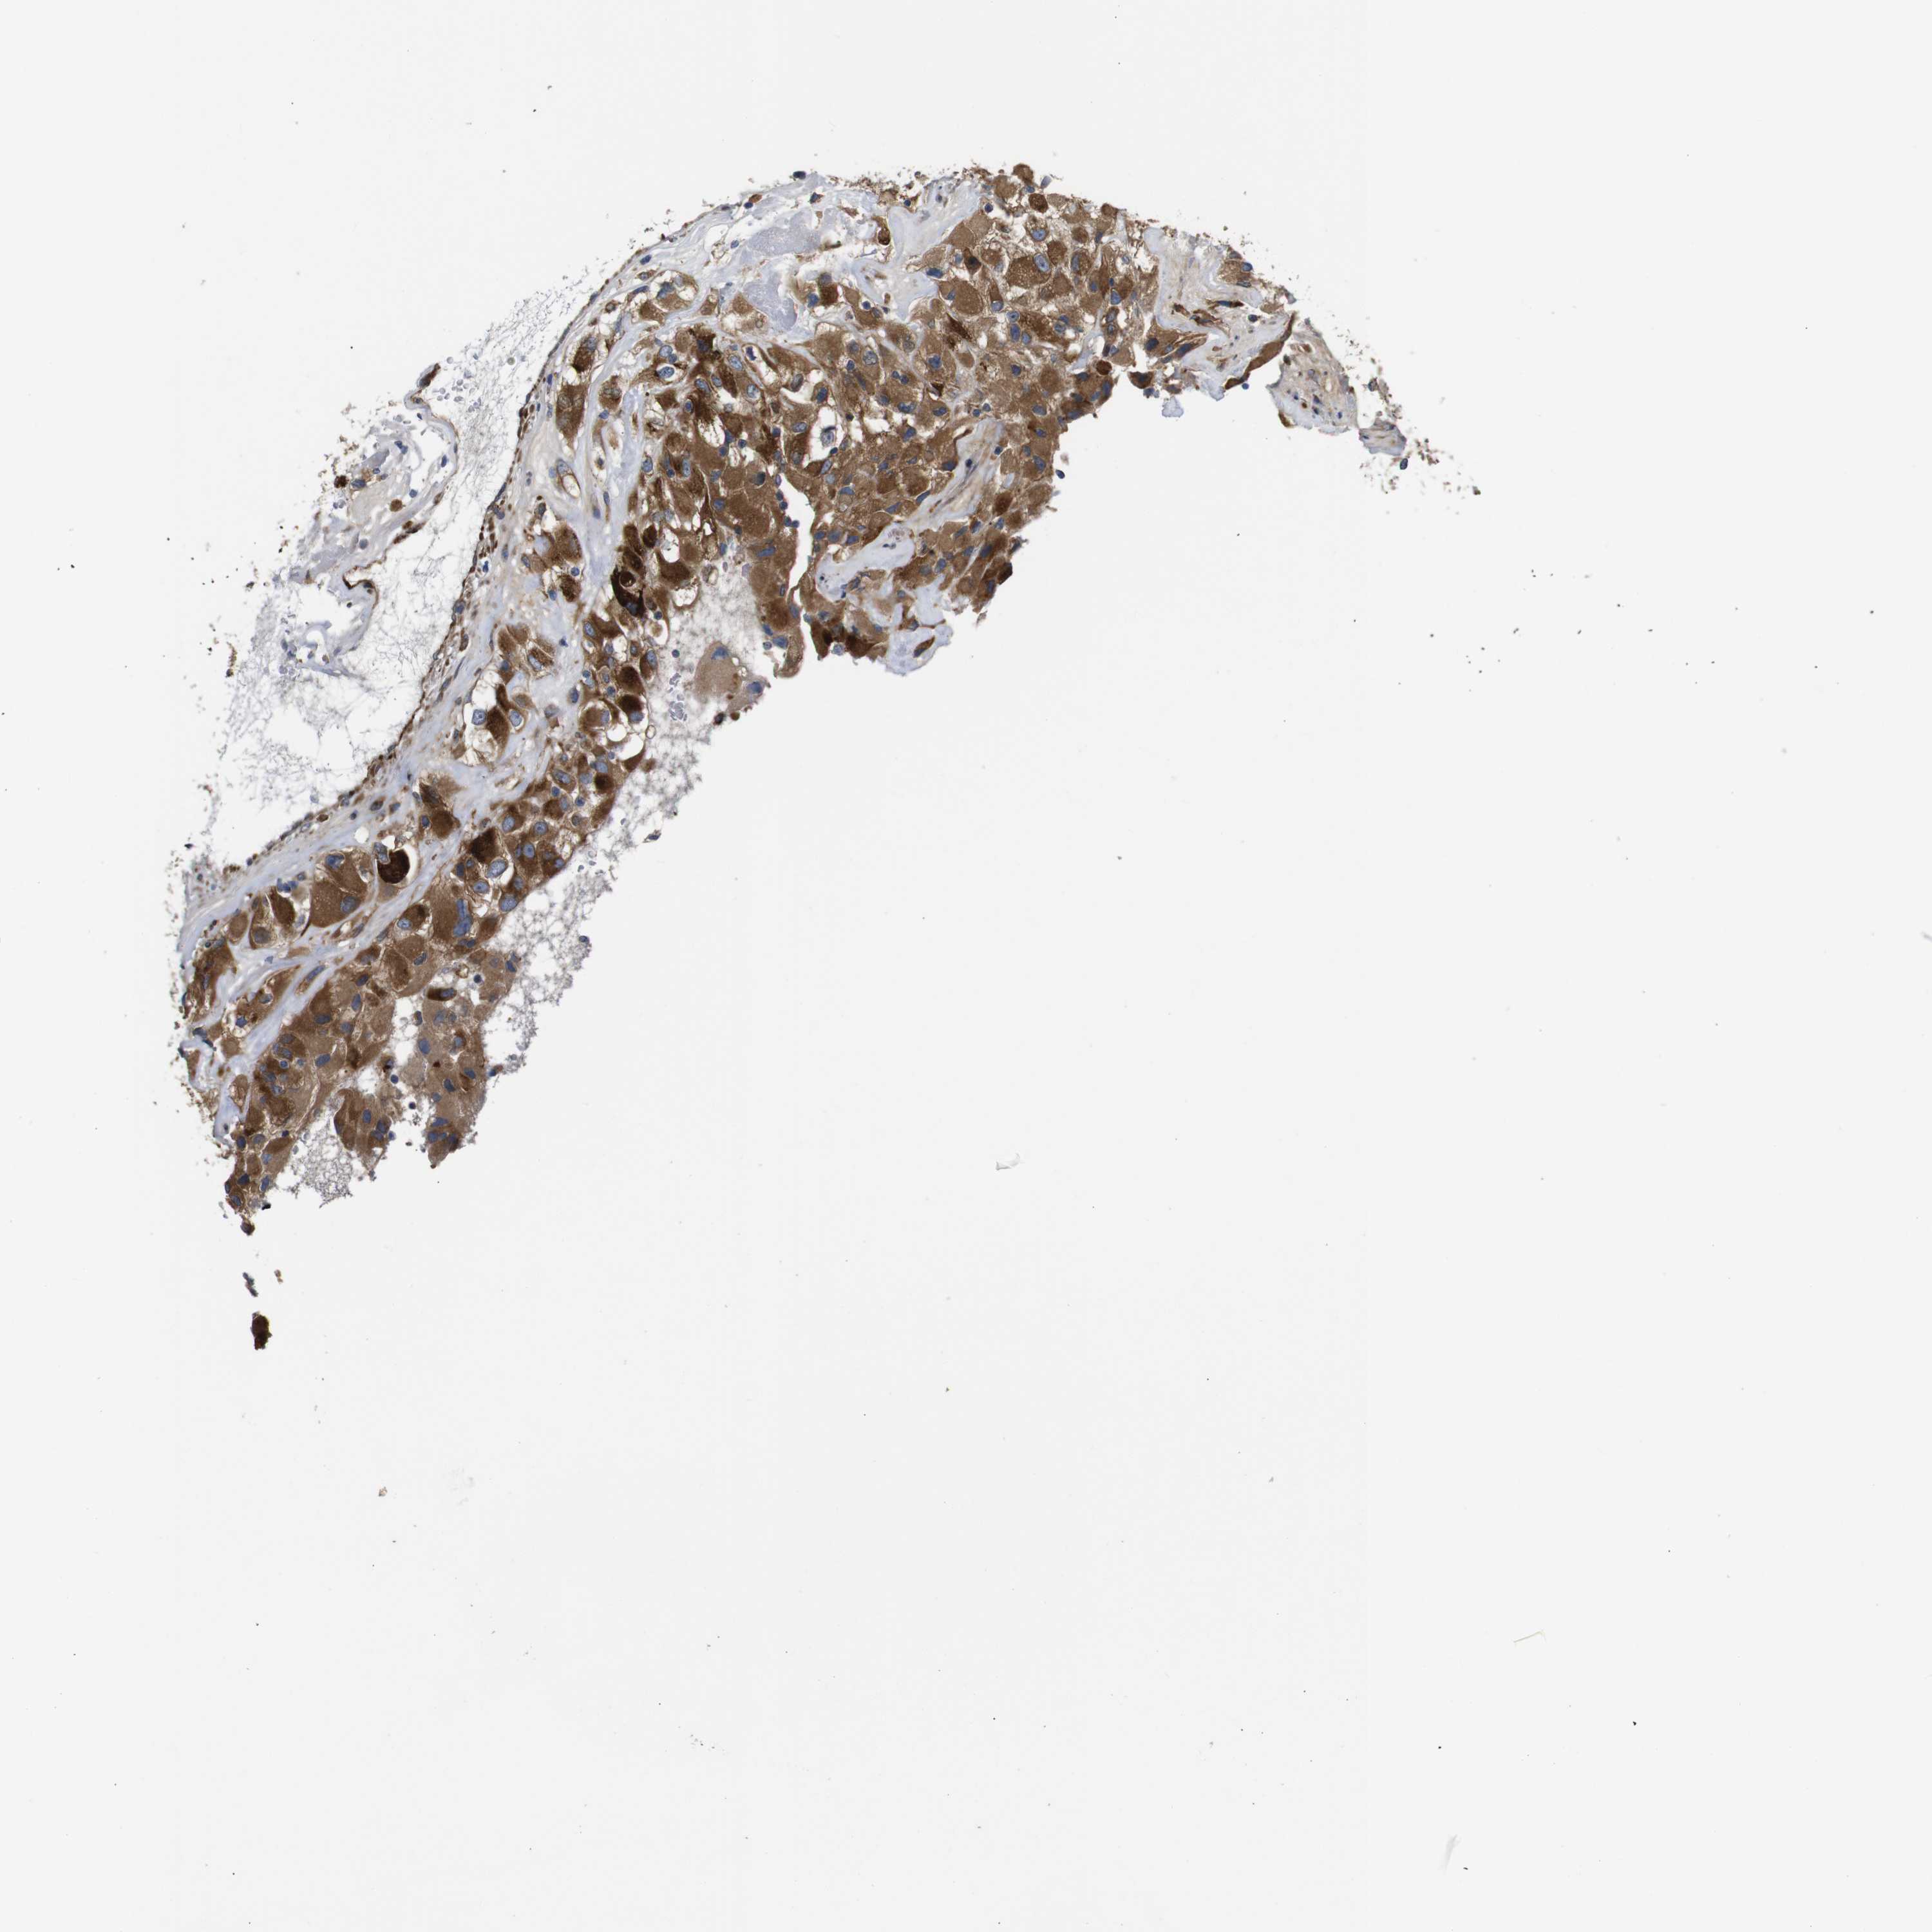

UBE2G2 is potential prognostic, high expression is favorable in Kidney Renal Clear Cell Carcinoma (TCGA)

Best expression cut offi

Based on the FPKM value of each gene, patients were classified into two groups and association between prognosis (survival) and gene expression (FPKM) was examined. The best expression cut-off refers the FPKM value that yields maximal difference with regard to survival between the two groups at the lowest log-rank P-value. Best expression cut-off was selected based on survival analysis .

When clicking on this number, the vertical dashed line indicating cut-off, the interactive survival plot, and the Kaplan-Meier curve will be adjusted to show results based on the best expression cut-off.

: 18.68

P scorei

Log-rank P value for Kaplan-Meier plot showing results from analysis of correlation between mRNA expression level and patient survival.

N/A

5-year survival highi

5-year survival for patients with higher expression than the expression cutoff.

For melanoma and glioma, 3-year survival is shown.

5-year survival lowi

5-year survival for patients with lower expression than the expression cutoff.

Average pTPM 26.6

Number of samples 521